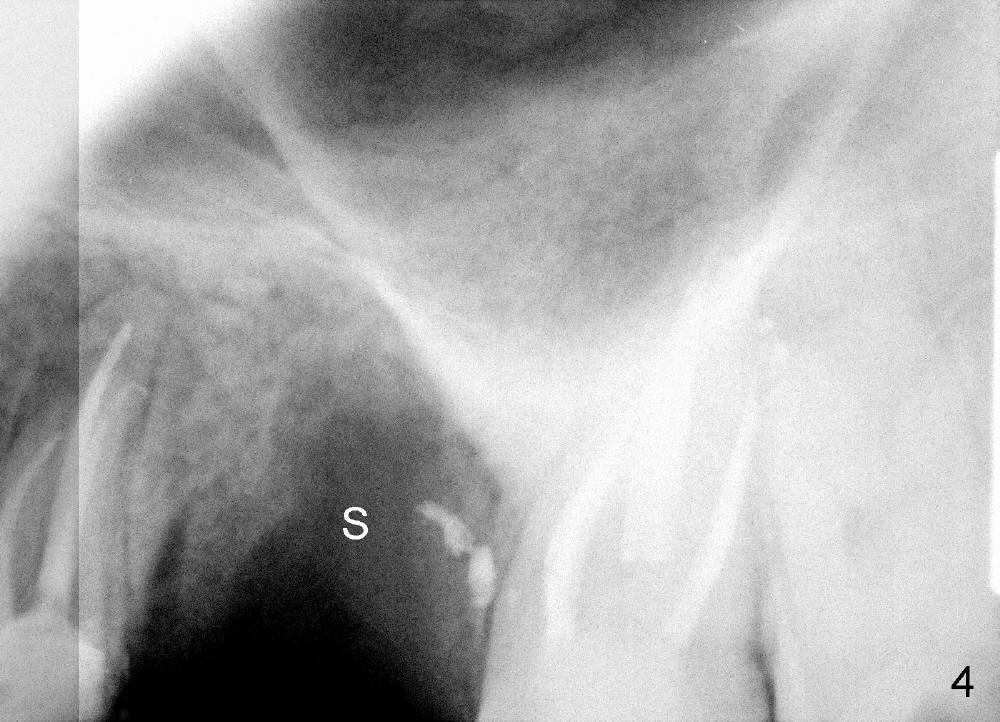

The socket looks empty two months post-extraction (Fig.4 S). Bone appears to re-grow in the socket 9 months after extraction (Fig.5 S), but the buccal plate is severely atrophic and concave (Fig.6 arrowheads). When an incision is made, the socket feels soft. Osteotomy is created by bone expansion (round tapered osteotomes (RT) 2,3,4 mm). Drilling is done once, using 3.5x17 mm tapered drill when the larger RTs meet resistance near the sinus floor. Tapered taps are used to continue to expand the osteotomy (4.5 (Fig.7), 5.0 and 6.0x20 at the depth of 17 mm). Finally 6.0x17 mm implant is placed with insertion torque more than 60 Ncm (Fig.8). The buccal plate is less concave with bone expansion and implantation (Fig.9 arrowheads). Without immediate implant, bone resorbs quick, which makes delayed implantation difficult.